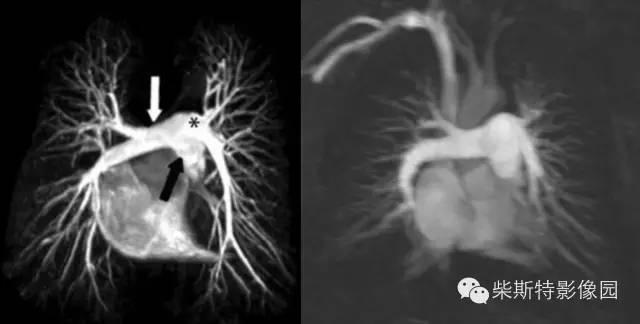

第三大名捕:肺动脉MRA

磁共振肺灌注成像(MRPP)

小编解析:

其实就论本领而言,肺动脉MRA与肺动脉CTA不相上下,二者各有千秋!只因肺动脉CTA速度上较其更快一些,故排名第二!